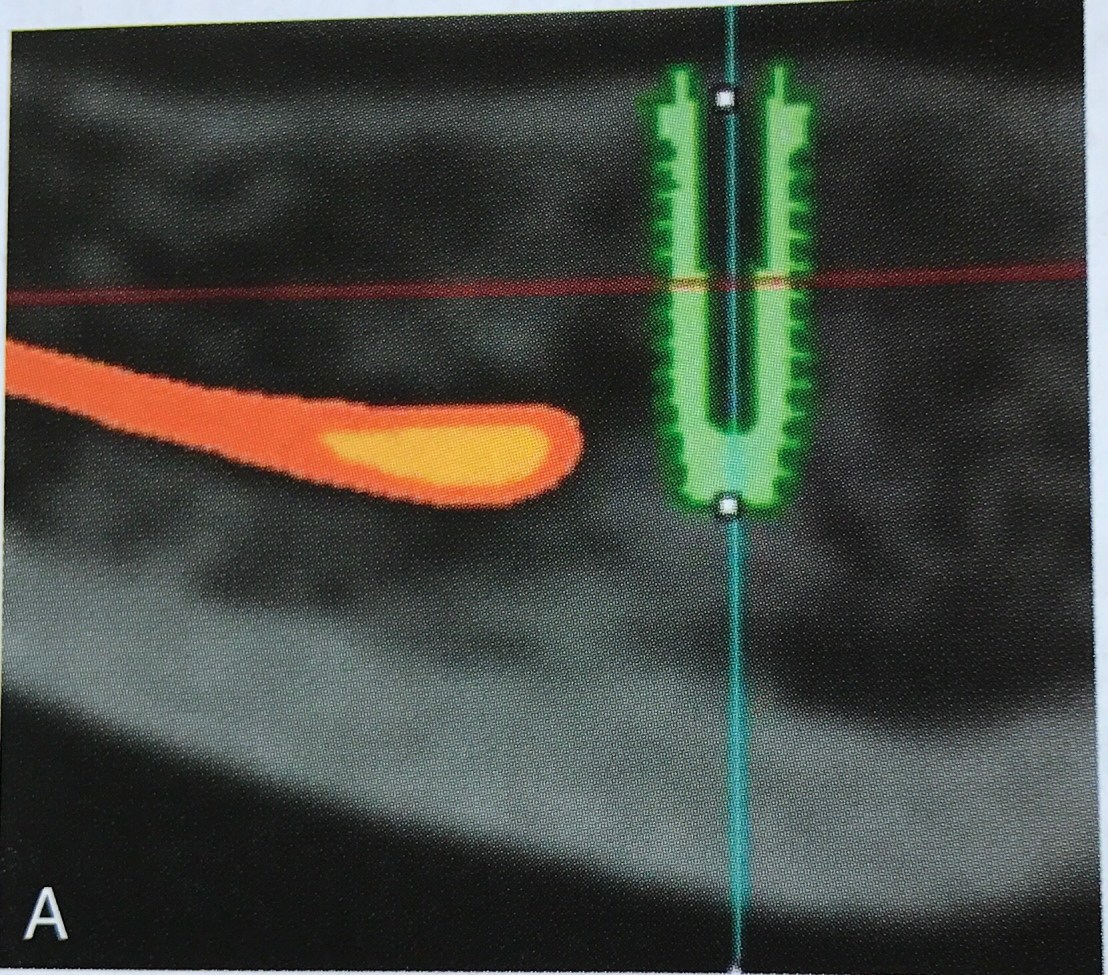

CBCT แสดงการ locate Mandibular canal

รูป A ภาคตัดขวางแสดง Mand canal มีขอบ calcify สีขาวล้อมรอบชัดเจน

รูป B ประมาณ 30% ของผู้ป่วย เราจะไม่พบ cortical bone lining รอบ canal เหมือนในรูป A ครับ

รูป C และ D คือ Panoramic view ของ CBCT